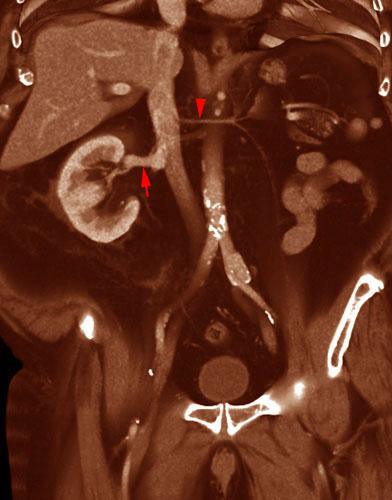

Agenesia Renal

VR seccional. Visión coronal anterior. Se observa un riñón derecho único con su vena renal (flecha) drenando en vena cava inferior. Vena renal izquierda hipoplásica (punta de flecha), confluencia de las venas suprarrenal izquierda y vena gonadal